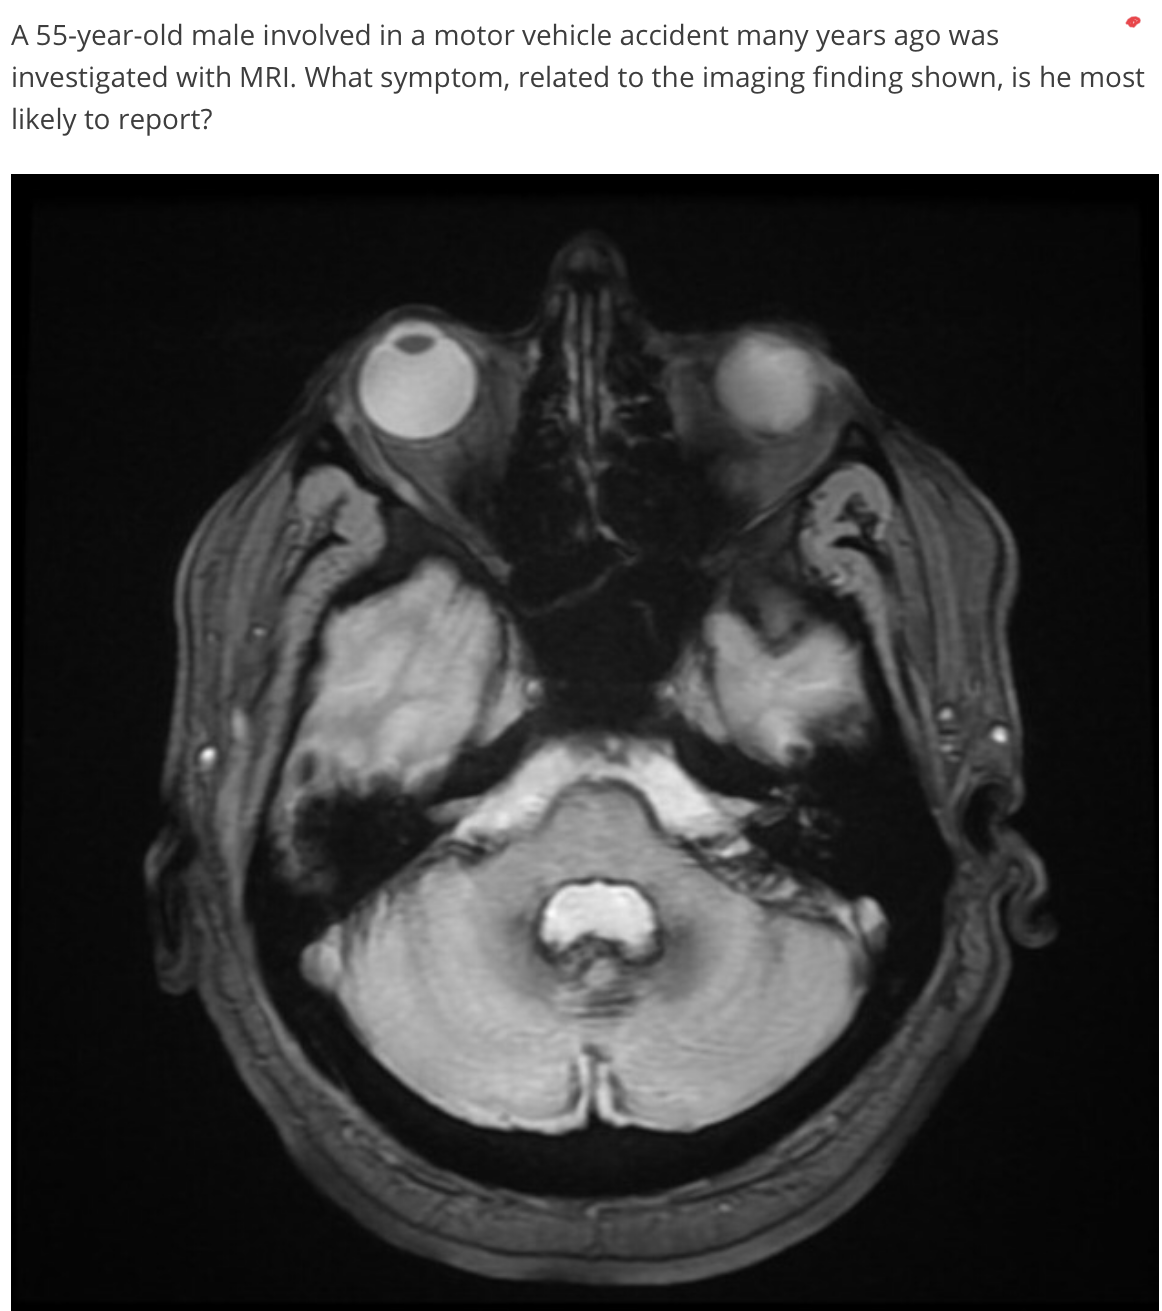

SUPERFICIAL SIDEROSIS - what is it?

HEMOSIDEROSIS - clinic?

SIDEROSIS

(symptoms: vertigo, tinnitus)